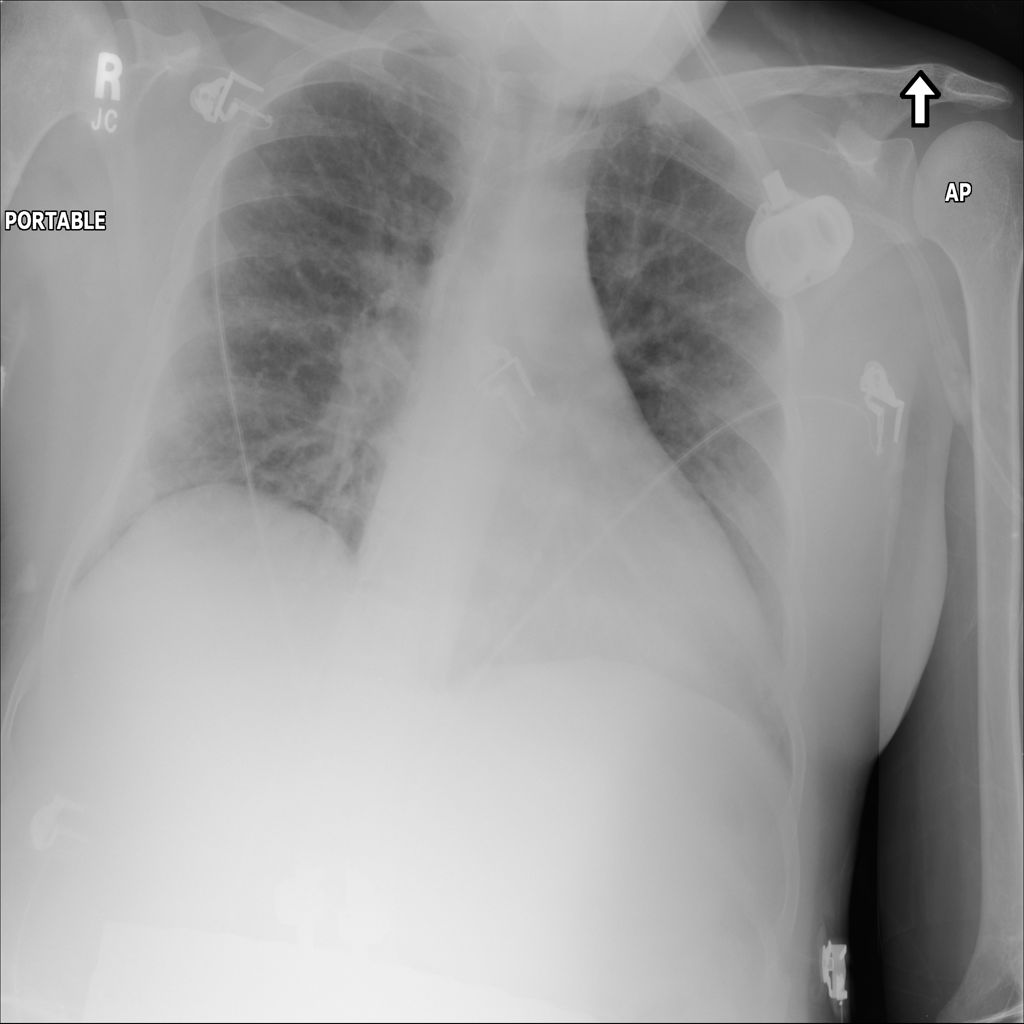

PAT-E828 · IMG-004Edema

PAT-E828 · IMG-004

AP